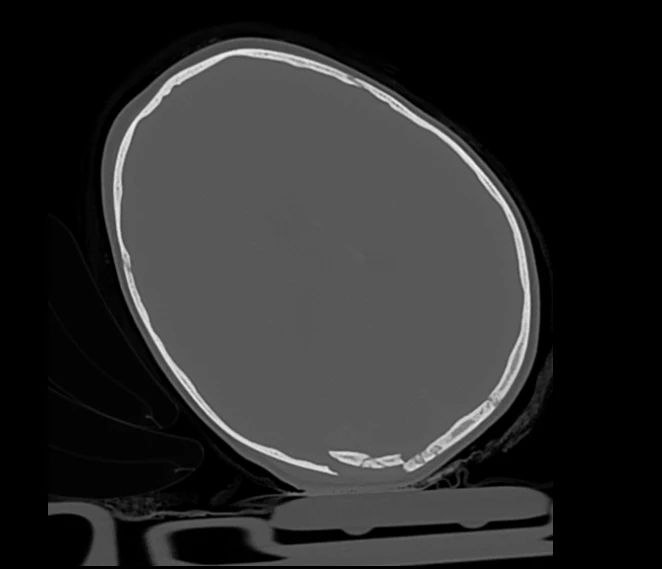

Как сообщают специалисты ДРКБ, сейчас ребенок находится в отделении анестезиологии и реанимации. У него черепно-мозговая травма и перелом бедренной кости. Врачи оказывают всю необходимую помощь, состояние маленького пациента крайне тяжелое.